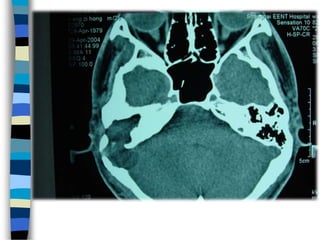

Оношлогоо Чихний тольдолт

Сонсголын шинжилгээ Нянгийн шинжилгээ Рентген КТГ СРТГ